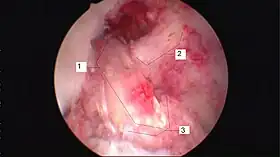

Arthroscopic anterior cruciate ligament (ACL) reconstruction (right knee). The tendon of the semitendinosus muscle was prelevated, folded and used as an autograft (1). It appears through the remnant of the injured original ACL (3). The autograft then courses upwardly and backwardly in front of the posterior cruciate ligament (2).